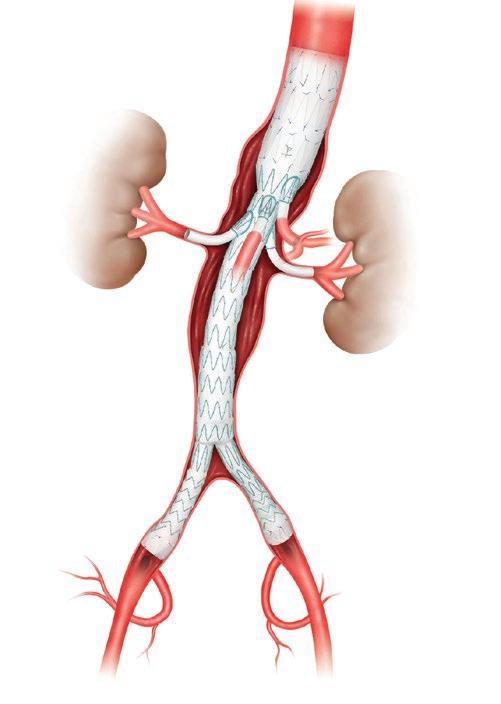

An artistic take on the image of a branched endograft to illustrate the essence of this device, which has transformed complex aortic aneurysm repair. Read about it on page 12. Based on the original photo taken by Matt Wright.

During a complex fenestrated or branched endovascular aortic aneurysm repair, the surgeon delivers a custom-made, expandable stent graft (above) to the area of the aneurysm. Small holes in the endograft are configured at the exact location of the branch arteries to accommodate the addition of smaller stent grafts to those arteries.

The minimally invasive FEVAR technique makes for safer and more effective repair of complex aortic aneurysms that include the arteries branching to the kidneys and intestines. The stent graft is designed to accommodate more complex aortic anatomy. Small holes in the endograft

are configured at the exact location of the branch arteries to accommodate the addition of smaller stent grafts to those arteries. The fenestrated endograft must align with the patient’s particular anatomy.